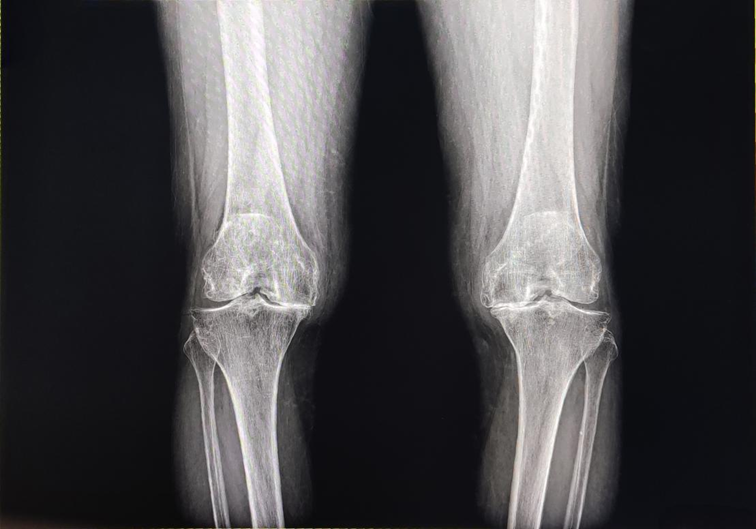

张阿姨深受膝关节炎困扰多年,近6年来病情愈发严重,不仅走路时关节剧烈疼痛,双腿还逐渐变形。“那时候两条腿弯得厉害,都成了‘罗圈腿’了,走路身子一摇一晃,别说干家务了,就连下蹲都做不到,每天都被病痛折磨,真是遭罪啊。”回忆起病情最严重的日子,张阿姨语气里满是感慨,眼里也泛起了泪光。